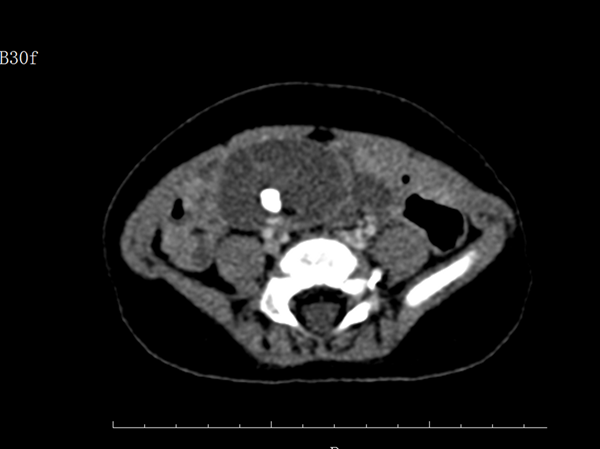

2019-11-278個(gè)月嬰兒患罕見(jiàn)睪丸畸胎瘤,腹腔鏡下成功摘除

近日,一名8個(gè)月大的嬰兒因左側(cè)隱睪來(lái)我院就診,門(mén)診彩超提示腹腔一液性包塊,考慮囊性畸胎瘤! 入院后通過(guò)完善腹部CT檢查,進(jìn)一步顯示腹腔內(nèi)的包塊...閱讀全文